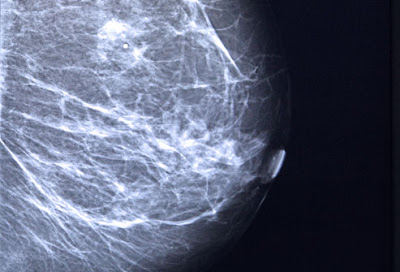

Breast Cancer and Mammograms

The earlier breast cancer is found, the easier it is to treat. And mammograms, X-rays of the breast, can detect tumors before they are large enough to feel. The American Cancer Society recommends yearly mammograms beginning at age 40 for women at average risk. While the U.S. Preventive Services Task Force recommends a screening mammogram every two years from age 50 to 74. It also notes that before age 50, each woman should check with a doctor to find out what screening schedule is right for her, considering the potential benefits and harms from screening.